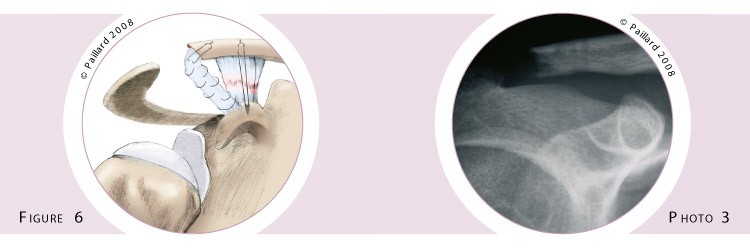

Si la chirurgie est pratiquée à distance du traumatisme, la faculté des ligaments à cicatriser sera dépassée. Il faudra alors remettre la clavicule à niveau et remplacer les ligaments rompus par un nouveau ligament. Il s’agit de la « ligamentoplastie ». Elle nécessite le plus souvent une incision courte en avant de l’épaule, mais peut parfois être réalisée sous arthroscopie. En plus de la stabilisation simple qui est faite par un système de fils résistants entre la clavicule et la coracoïde, un remplacement ligamentaire est effectué. Pour cela, l’extrémité de la clavicule est sectionnée (figure n°5). Le ligament acromio-coracoïdien, qui est un ligament accessoire tendu entre la coracoïde et l’acromion, est détaché de ce dernier. Il est ensuite fixé dans la tranche de section de la clavicule, remplaçant ainsi les ligaments rompus (figure n°6, photo n°3).